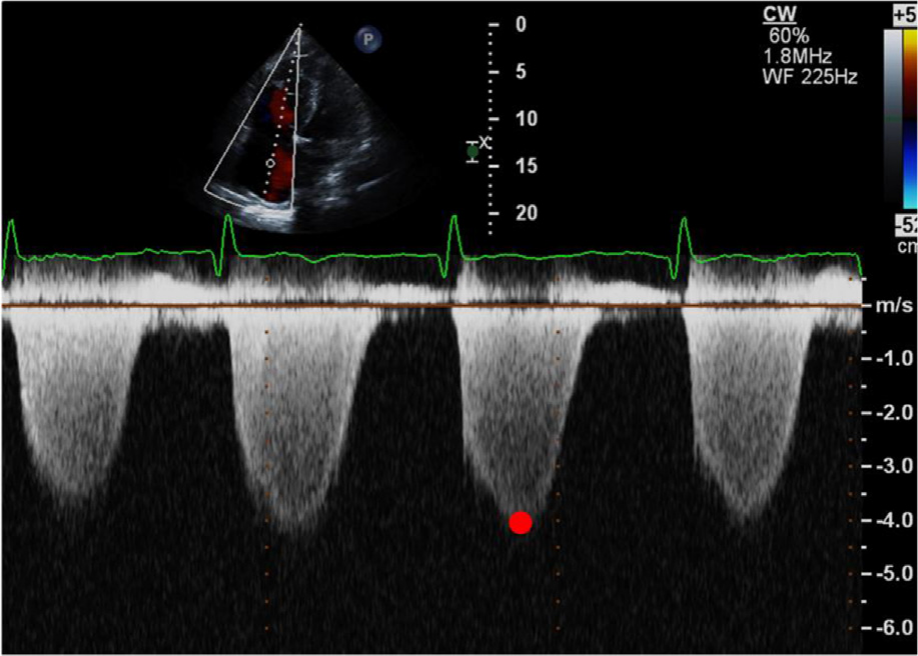

1. 三尖瓣反流计算法

对合并有三尖瓣反流的患者,采用连续波多普勒测量三尖瓣最大反流速度,依据简化的伯努利方程计算跨瓣压差(△PTR)。为避免测值被高估,应该确保收缩期峰值流速测量来自频谱多普勒的浓密部分。为确保准确性并考虑呼吸影响,应从速度最高且多普勒包络最清晰的窗口取至少3 个连续心动周期的平均值计算。

△PTR=4Vmax2

在没有右心室流出道梗阻或肺动脉瓣狭窄时,收缩期右心室内压力(SRVP)与肺动脉收缩压(SPAP)近似相等。SRVP可通过三尖瓣口跨瓣压差与右心房内压力(RAP)间接获得,故SPAP也可以通过三尖瓣口跨瓣压差进行评估。

SPAP=4Vmax2+ RAP

根据三尖瓣反流计算肺动脉收缩压(图A),三尖瓣反流速度越高,肺动脉收缩压越高(图B)

RAP代表右心房压力。右心房大小正常,轻度三尖瓣反流时,RAP约5mmHg;右心房轻度增大,中度三尖瓣反流时,RAP约10mmHg;右心房明显增大,重度三尖瓣反流,RAP约15mmHg。RAP还可以通过下腔静脉内径及其随呼吸变化率进行评估。